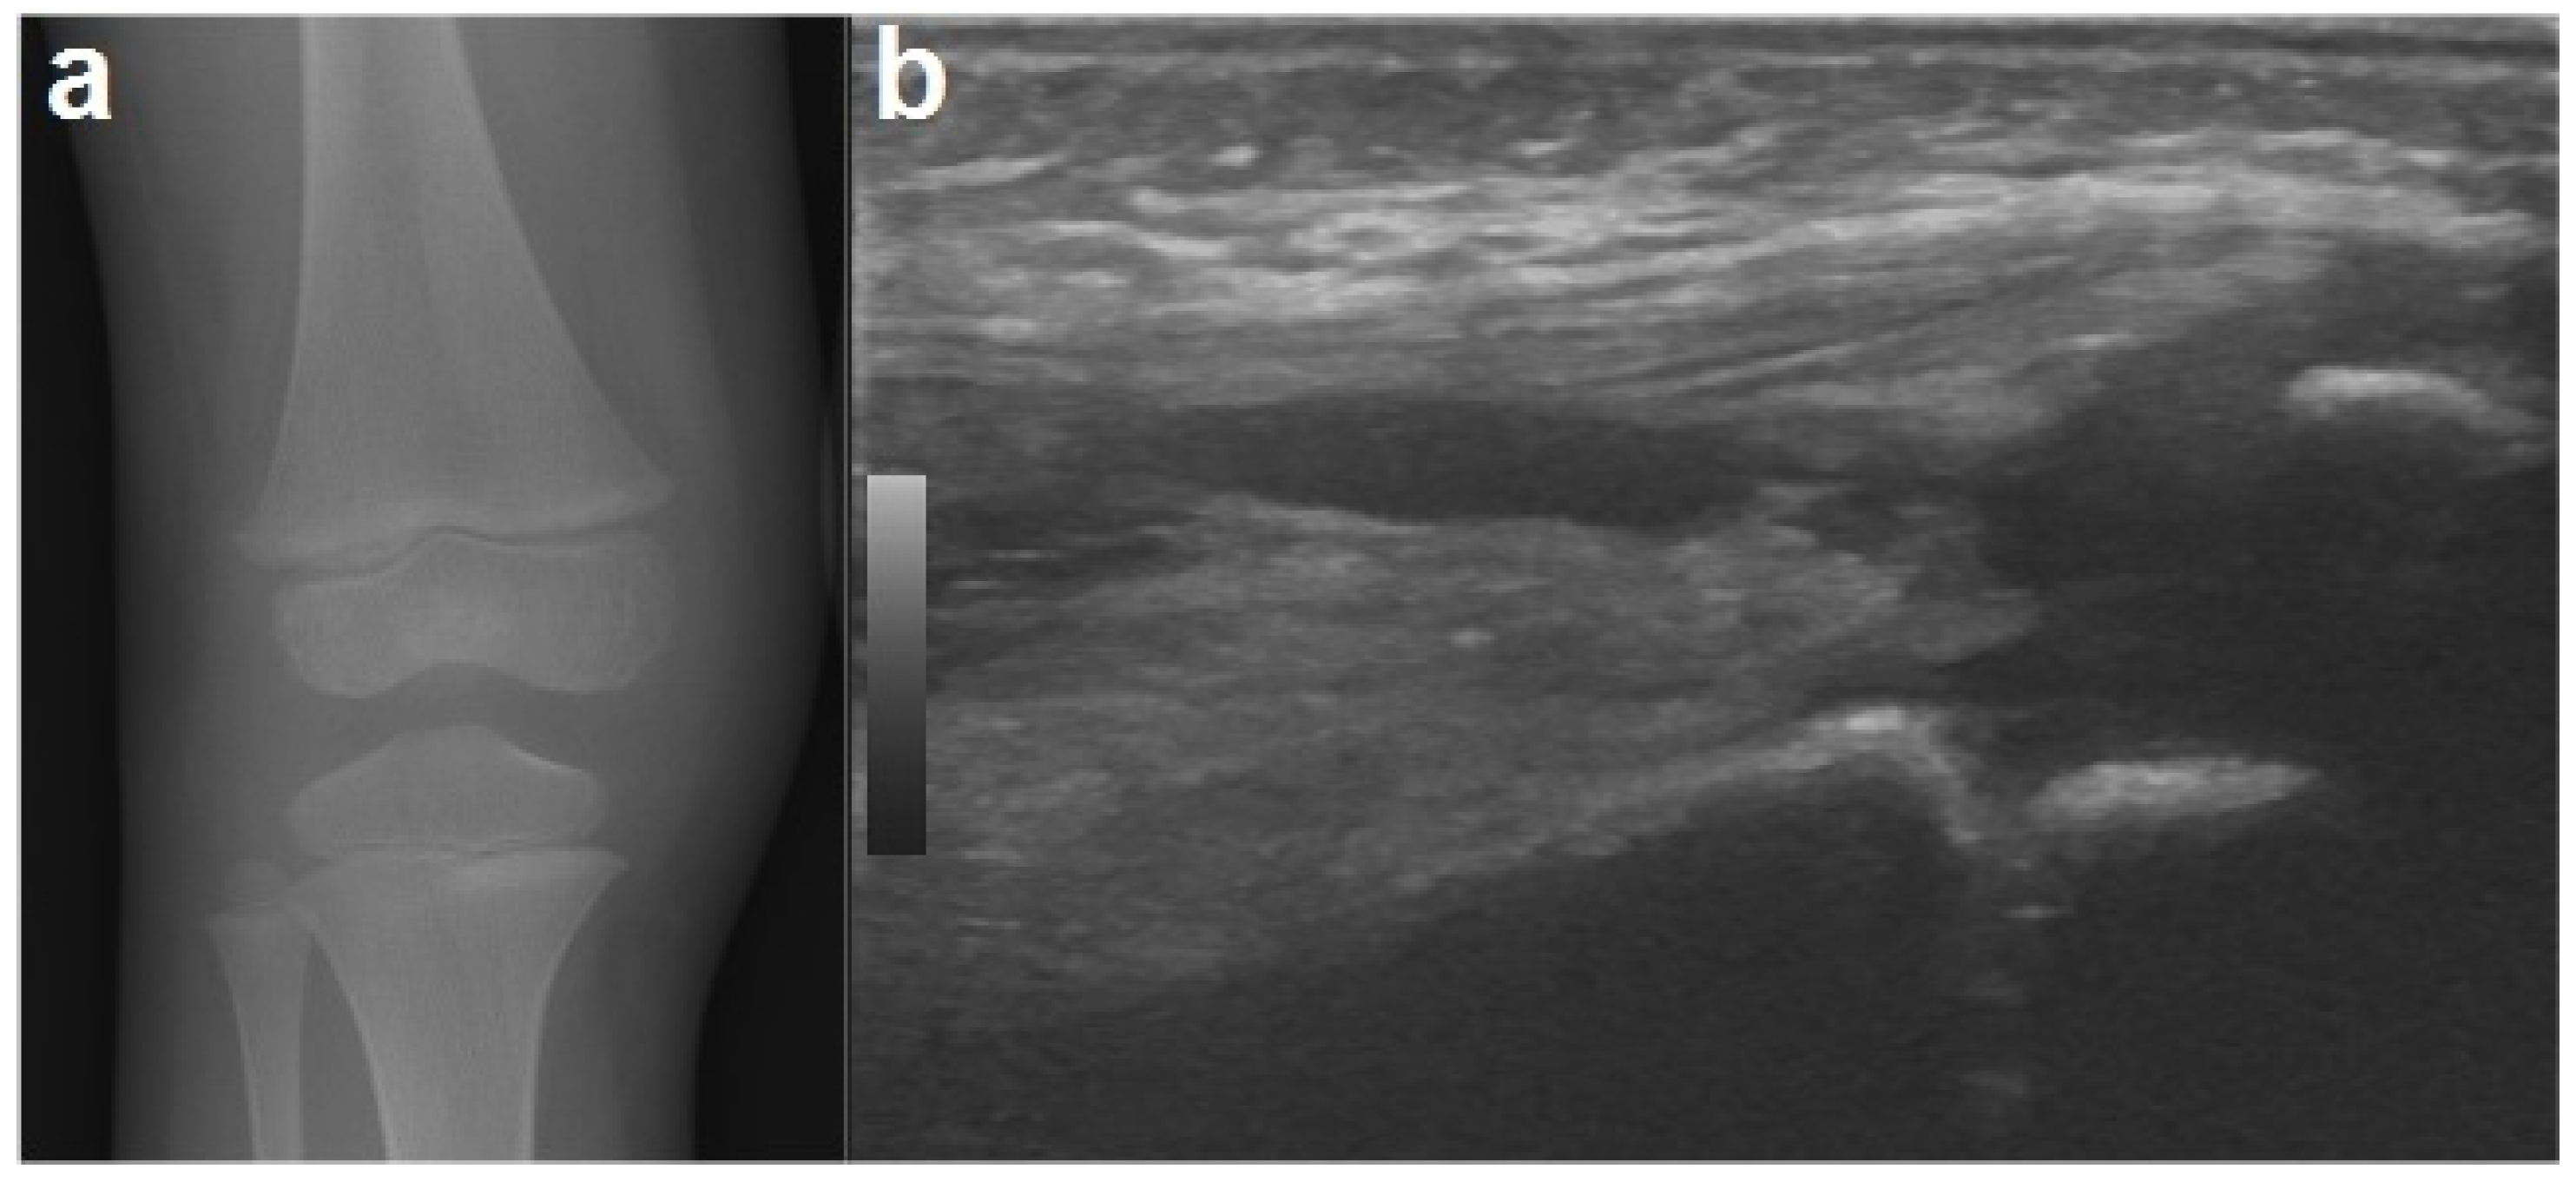

2. Case Report